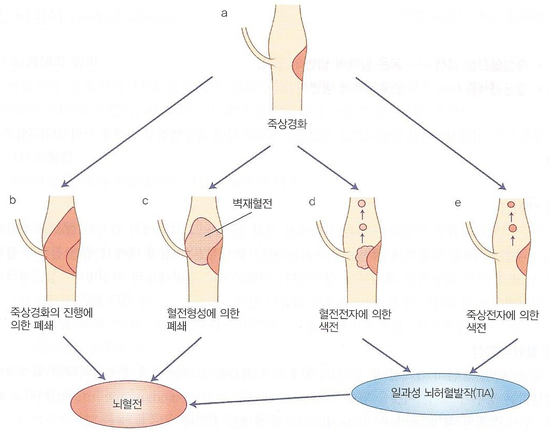

죽상경화(동맥경화) 혈전생성은 죽상경화(동맥경화)에서 비롯되며 죽종이라는 것은 혈관 안쪽에 형성된 죽처럼 끈질긴 병변입니다. 죽상경화가 그대로 커져 혈관을 폐쇄하는 경우도 있지만 대부분은 죽종에 다시 혈소판이 부착돼 혈전을 생성하고 이런 모양의 벽재혈전이 혈관을 폐쇄합니다.

동맥경화(죽상경화)와 뇌혈전혈전, 색전생성의 다양한 경로는 위 그림과 같습니다. 혈전의 일부나 죽종의 일부가 떨어져 혈류 하부에 쌓여 일과성으로 증상을 보이는 경우가 있는데, 이를 일과성 뇌허혈발작(TIA)이라고 하며 뇌경색이 발생할 조짐이 있으므로 주의 깊게 관찰해야 합니다.

혈전은 비교적 천천히 동맥의 협착과 폐쇄를 일으킵니다. 그리고 어느 정도 두께의 동맥이 폐쇄되느냐에 따라 혈전성 뇌경색과 열공성 뇌경색으로 구분합니다. 전자는 비교적 굵은 동맥(전·중·후대뇌동맥)에 발생하고 후자는 관통동맥(교합혈관이 없는 동맥)에 생깁니다.

2) 색전 색전은 폐쇄 혈관 부위와 다른 곳에서 생긴 혈전이 흘러들어와 갑자기 혈류를 막는 것입니다. 대부분은 심장 내에서 생긴 혈전이 혈류를 타고 흘러 뇌동맥을 폐쇄합니다. 심판막증이나 심방세동의 좌심방벽, 심근경색의 수심실벽에서 발생하는 혈전 등이 뇌경색의 원인이 됩니다.뇌혈전(혈전성, 열공성)과 뇌색전의 차이는 아래 표와 같습니다.